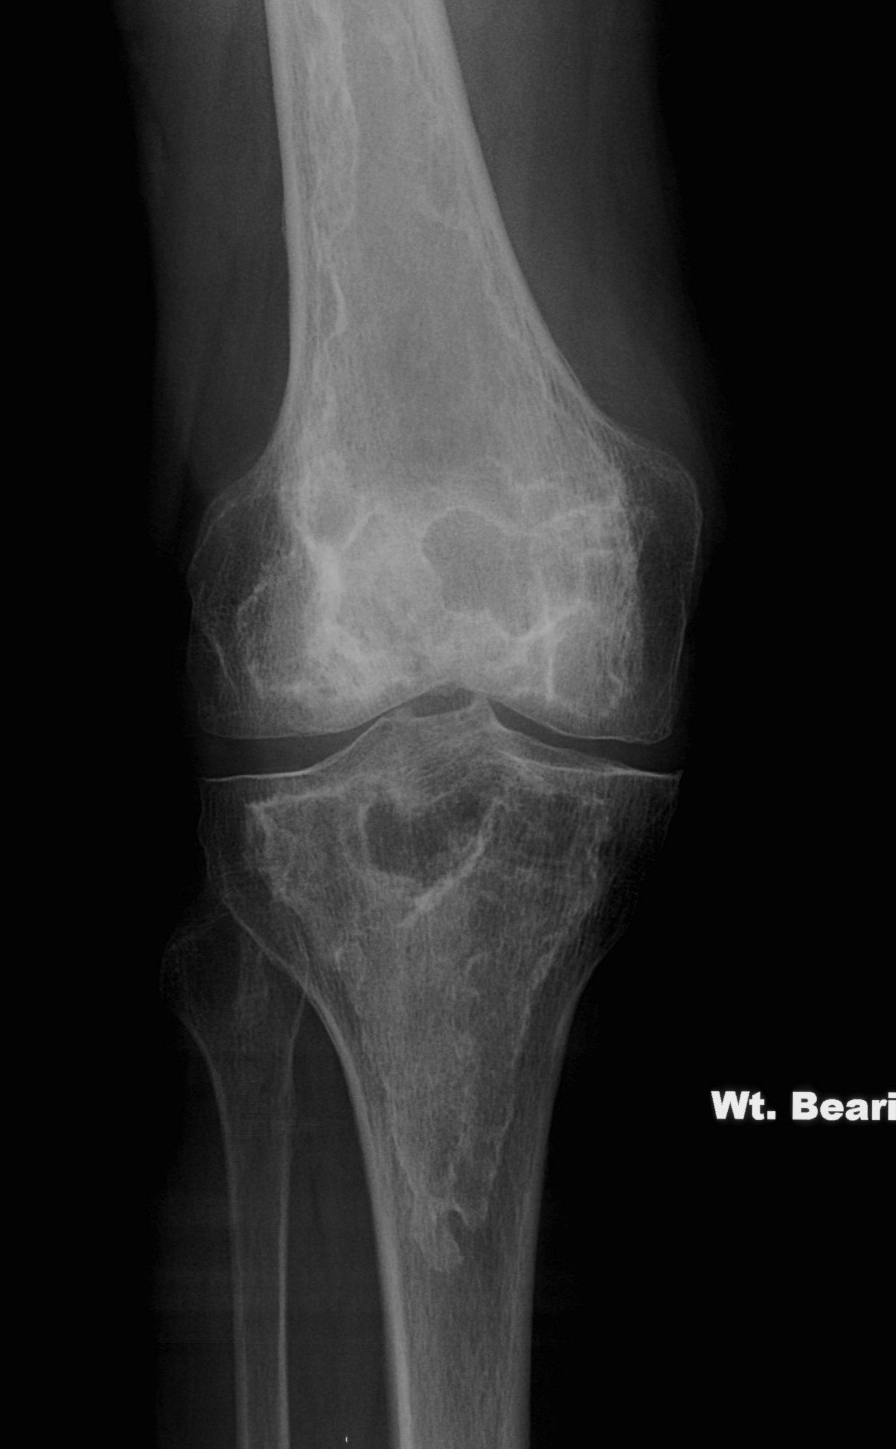

Prognosis

Pleomorphic sarcoma may arise from long standing bone infarcts